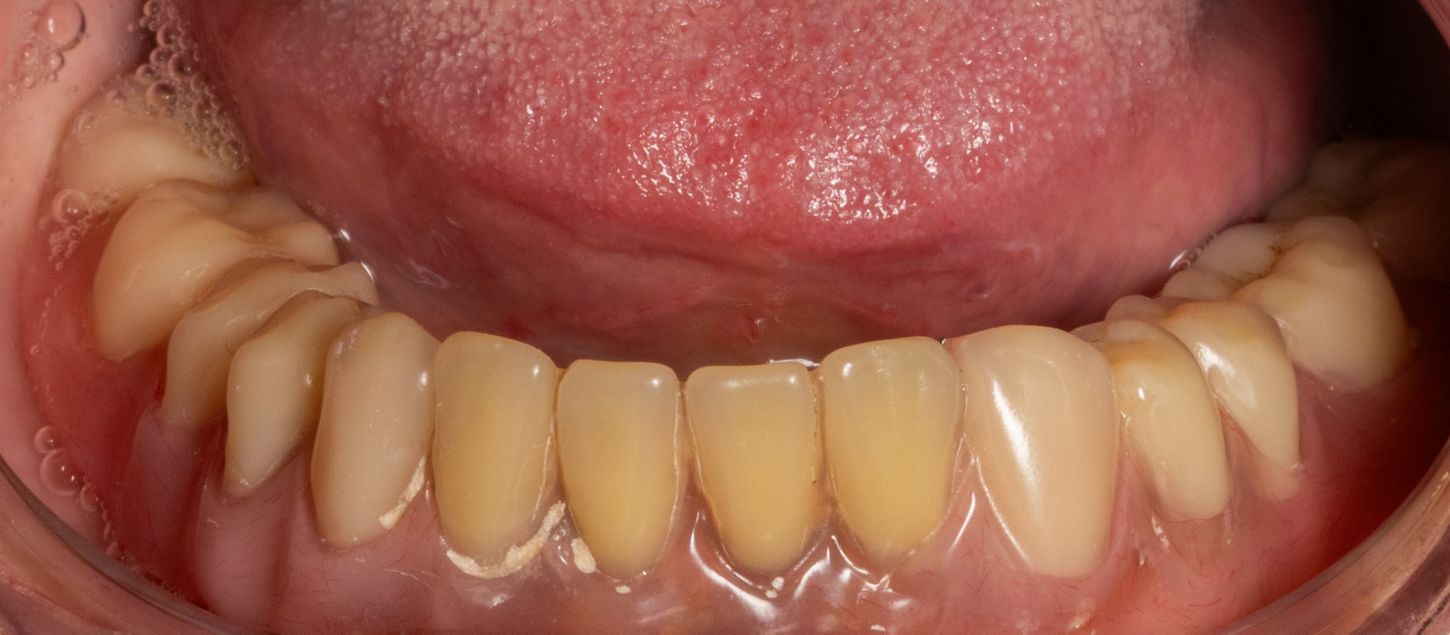

2c. Situation in the mandible: thin alveolar crest and residual teeth 33 and 43.

2c